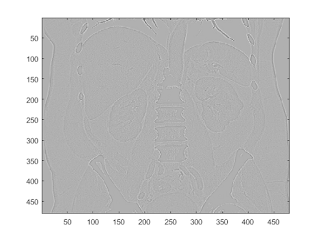

laplacian

clf b = fspecial('laplacian'); I2 = conv2(I,b,'same'); imagesc(I2);